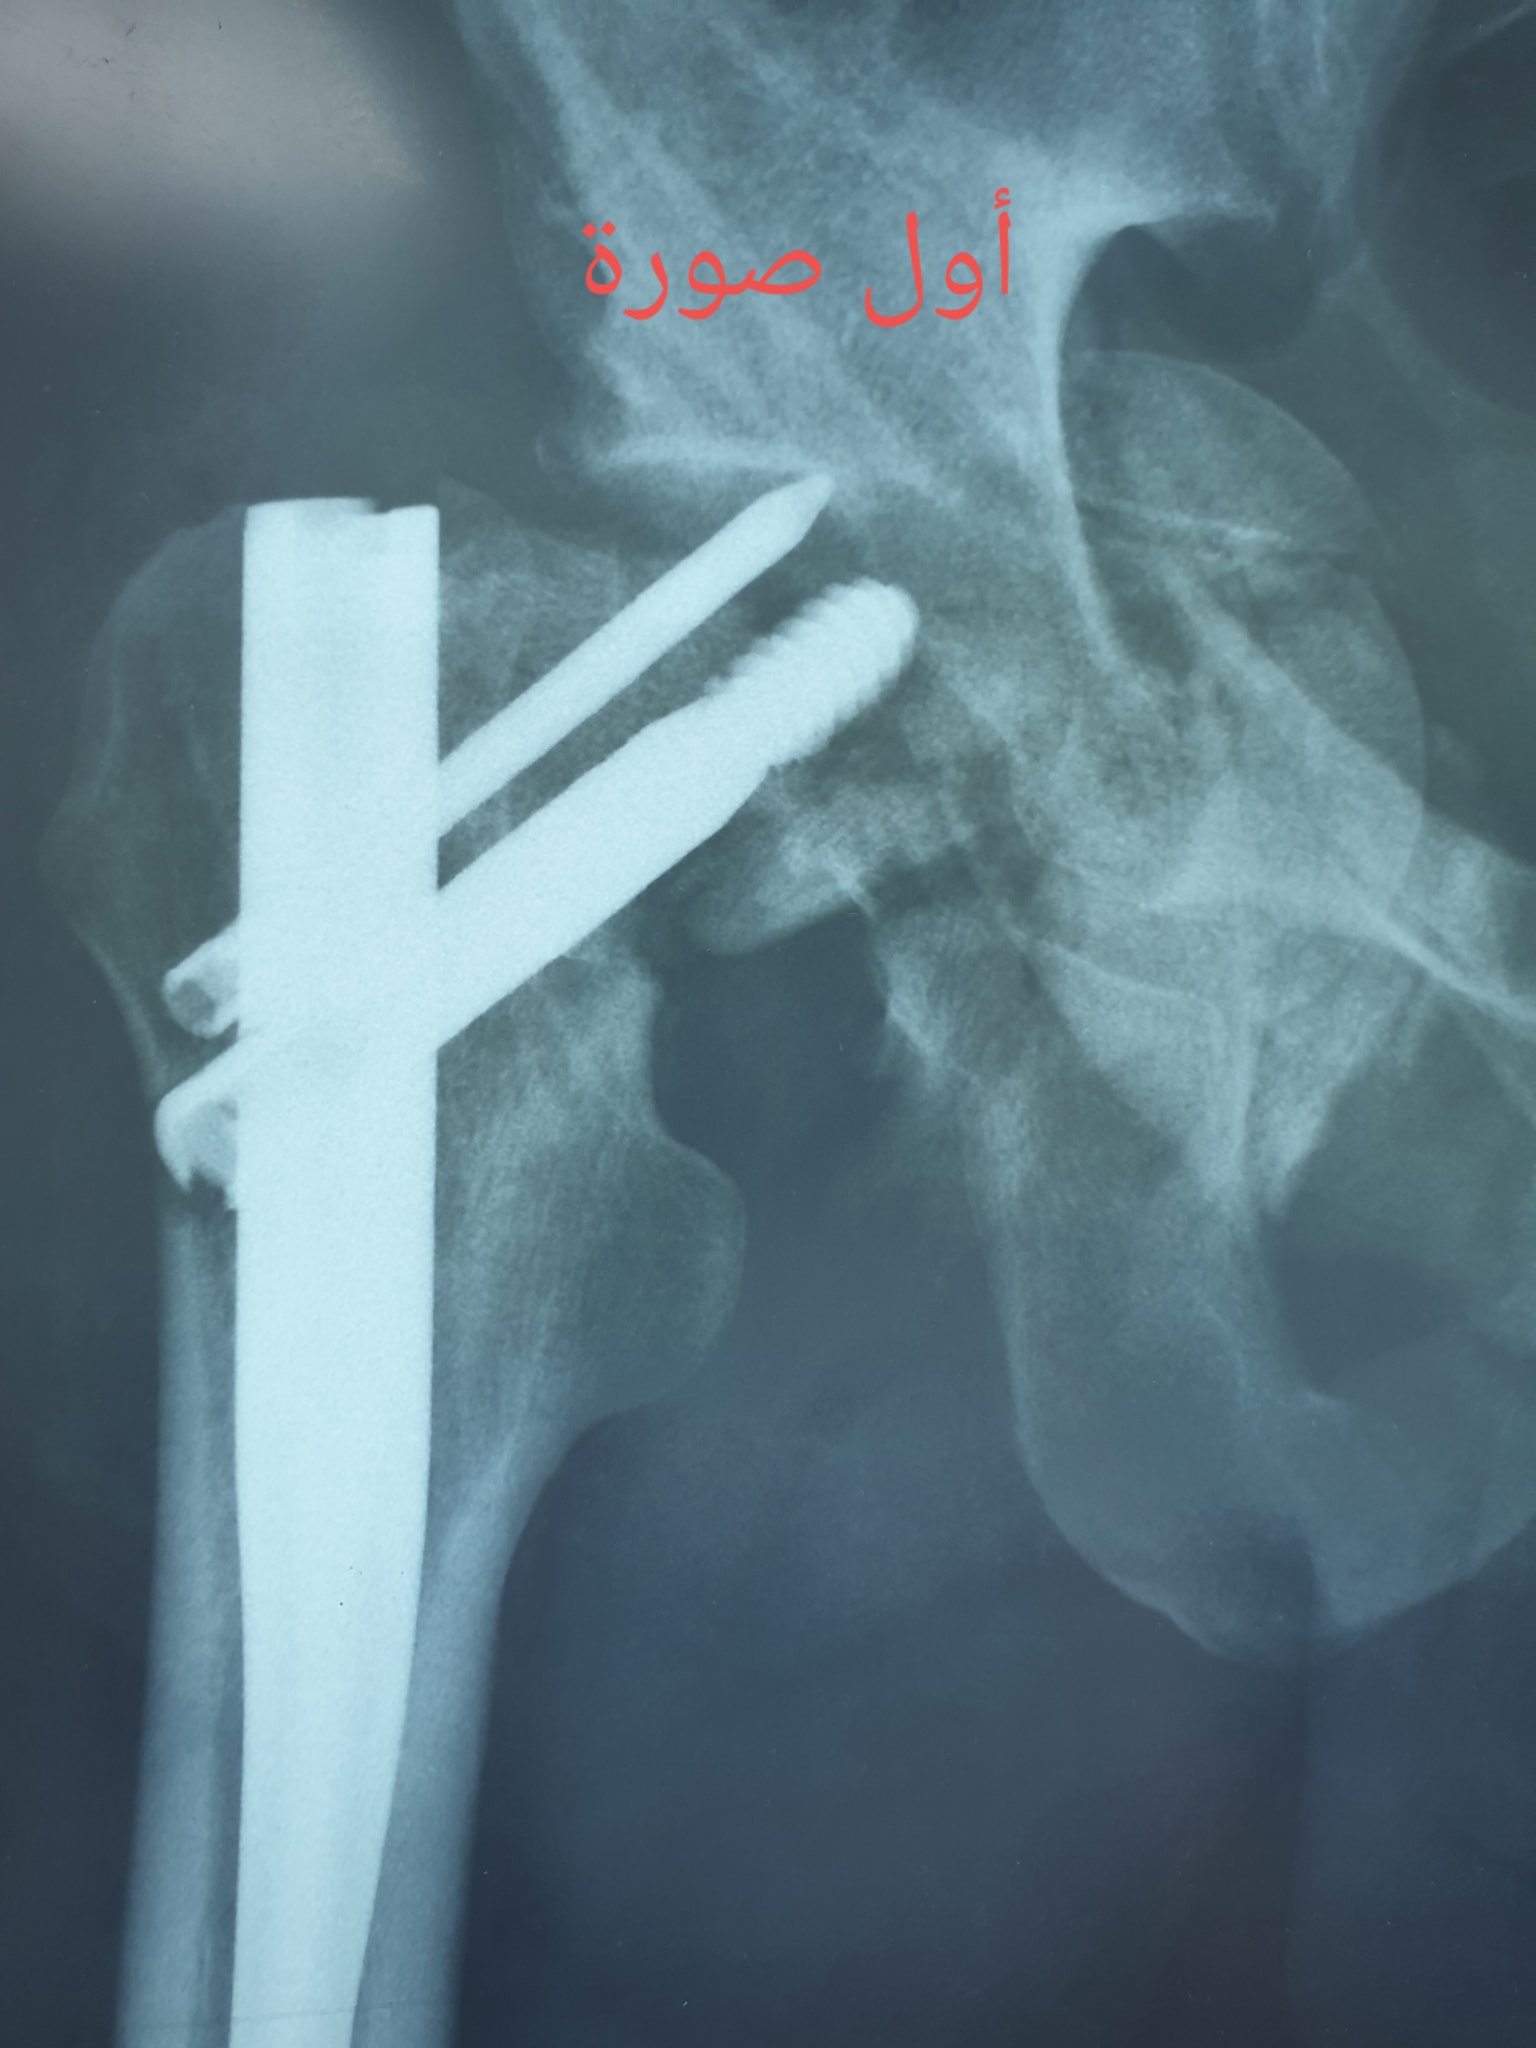

كافة انواع الكسور وعلاجها